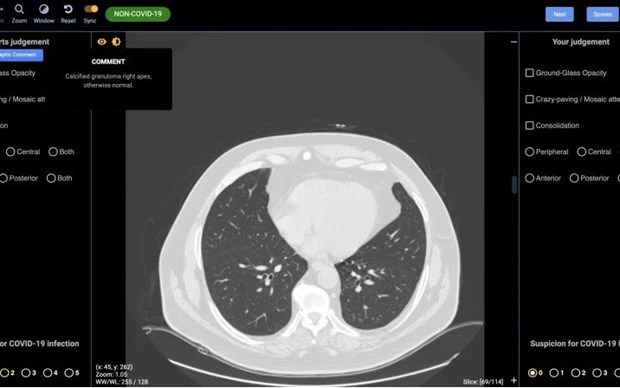

CovED cho phép chẩn đoán chính xác những người nhiễm SARS-CoV-2 nhờ phương pháp phân tích h́nh ảnh chụp cộng hưởng từ (CT) phổi của bệnh nhân.

Các nhà khoa học Australia đă thiết lập thành công một công cụ chẩn đoán h́nh ảnh trí tuệ nhân tạo (AI), hỗ trợ lực lượng nhân viên y tế trong việc xác định chính xác người nhiễm virus SARS-CoV-2 gây dịch bệnh viêm đường hô hấp cấp COVID-19.

Công ty khởi nghiệp DetectED-X, liên kết với Đại học Sydney, đă công bố một công nghệ mới, gọi là CovED, cho phép chẩn đoán chính xác những người nhiễm SARS-CoV-2 nhờ phương pháp phân tích h́nh ảnh chụp cộng hưởng từ (CT) phổi của bệnh nhân.

Giám đốc điều hành DetectED-X, Giáo sư Patrick Brennan, cho biết công nghệ AI mới hỗ trợ các chuyên gia h́nh ảnh trong lĩnh vực y tế, đọc hiểu và phân tích cặn kẽ những ảnh hưởng ở phổi của người được chụp CT, dựa trên một hệ thống AI có khả năng kết luận chính xác về việc liệu người được chẩn đoán có bị nhiễm SARS-CoV-2 hay không. Mọi thao tác và kết quả chuẩn đoán sẽ có sau khoảng một giờ hoạt động.

Giáo sư Brennan nói, bên cạnh các phương pháp xét nghiệm dựa trên phân tích dịch mũi, họng hoặc xét nghiệm máu, phương pháp chụp cộng hưởng từ phổi cũng cho kết quả chính xác về việc liệu người được xét nghiệm có mắc COVID-19 hay không.

Do đó, CovED sẽ cung cấp những phân tích thay thế bác sỹ X-quang, trong t́nh huống có quá nhiều bệnh nhân và không đủ nhân viên y tế, để xác định chính xác tổn thương phổi do virus SARS-CoV-19 gây ra.